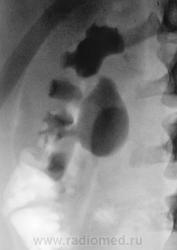

Пациент направлен на внутривенную урографию

Пациент направлен на внутривенную урографию.

Находится в хирургическом отделении. В отделение направлен из военкомата. Произведено стандартное исследование.

Пациент был прооперирован в 2009 году по поводу стриктуры в области лоханочно-мочеточникового сегмента справа.

Вероятнее всего, добавочный сосуд справа. А отсроченного снимка нет?

Отсроченного снимка нет, но есть томограммы. которые являются фактически отсроченными.

Да, правый мочеточник проходим, это доказали томограммы.

Мне показалось, что имеет место быть перегиб самой лоханки.

В принципе, мы "режем" все, и в прямой, и в боковой проекциях. В данном случае показалось, именно, за счет перегиба лоханки, что имеется крупный конкремент в лоханке, и я ожидал получить, что-то в виде "дефекта наполнения". История, как и в большинстве случаев, чистая. Потом заставил пациента принести копию выписки из областной больницы. Выписка конечно "не блещет", но удалось выудить, что пациент был оперирован по поводу гидронефроза, который был обусловлен стриктурой.